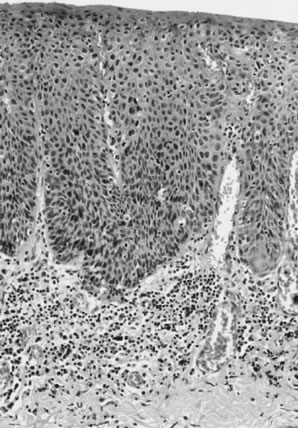

Histologic subtypes of squamous cell carcinomas are listed in Table 8. Squamous cell carcinomas with keratin pearls and obvious squamous cellular characteristics are considered well differentiated (Fig. 10). This pattern is usually the most frequent histologic type encountered. Other terms that have been suggested for the keratin pearl-forming carcinomas include large cell keratinizing, keratinizing, and epidermoid carcinoma. These tumors are more common in older women and are usually not associated with HPV.1,10 The less well-differentiated squamous cell carcinomas are less obviously squamous in origin without prominent intercellular bridges or keratinization (Fig. 11).

Fig. 11. Poorly differentiated squamous cell carcinoma of the vulva. The tumor cells are nonkeratinized, without prominent intercellular bridges. The tumor has a “finger-like” pattern of invasion.